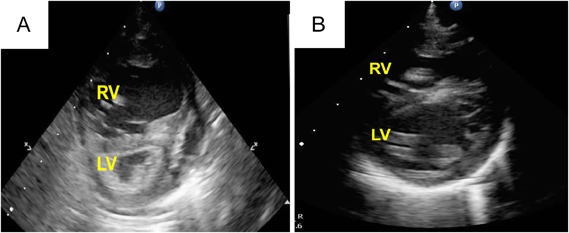

Fig. 2 (A) Preoperative and (B) postoperative echocardiography in Case 1

(A) The RV was remarkably dilated, with a flattened interventricular septum. (B) The deformity of the interventricular septum was improved. RV: right ventricle, LV: left ventricle

At 36 days of age, right PAB was performed through a median sternotomy using a 2-mm-wide expanded polytetrafluoroethylene (ePTFE) tape. The right PA was gradually tightened to a circumference of 14.5 mm with the band. At that time, the peak blood flow velocity across the right PA was 4.2 m/s. The systemic arterial pressure was finally elevated to 20 mmHg under 100% oxygen and nitric oxide (NO) inhalation. After this surgery, we were able to start aggressive PH therapy using tadalafil and macitentan to improve RV function. This patient was extubated on postoperative day (POD) 24, and NO inhalation was discontinued on POD 32. Echocardiography showed that the deformity of the intraventricular septum had improved, and the TR was trivial with a pressure gradient of 42 mmHg (Fig. 2B). Postoperative cardiac catheterization after right PAB demonstrated that the left pulmonary vascular resistance (PVR) was still high at 10.7 units·m2. However, her left lung reacted well to oxygen supplementation, and the patient was therefore considered to be a good candidate for total correction. After the development of bacterial pneumonia, her cardiac function and PH deteriorated, and mechanical ventilation was required on POD 45. After improvement of the PH and heart failure by antibiotic therapy, total correction was achieved 72 days after the initial palliation.